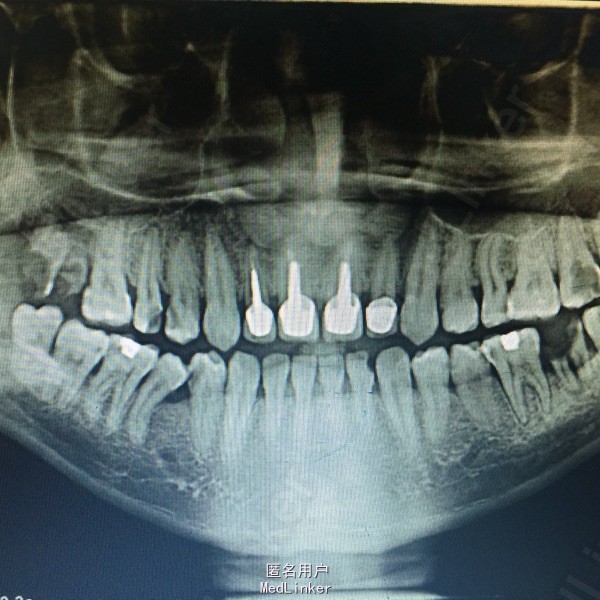

主诉:患者右上后牙不适数日。 病史:数日来,患者右上后牙疼痛,左侧极少咀嚼影响进食,来院就诊。

查体:14,15邻面之间龋坏,洞底有大量软化牙本质,探(+),冷热诊疼痛明显且持续较长时间。叩(-),X线示龋坏深达牙髓腔。17,37残冠,26牙合面大面积龋坏,探(+)冷(+)叩(-),X线示龋坏深达髓腔。 患者血压,血糖在正常范围,其余满足拔牙适应症。

诊断:14,15,26牙髓炎17,37残根 治疗: 局麻下14,15去腐,开髓揭髓顶降牙合,冲洗髓腔,拔髓疏通根管,测量根管配合EDTA进行根管预备,次氯酸钠进行根管冲洗,吸潮纸尖拭干根管,进行根管试尖,X线示恰充,进行热牙胶垂直加压连续波充填法进行根管充填。暂封观察进行树脂嵌体修复。分次拔除17,37.嘱拔牙后注意事项。